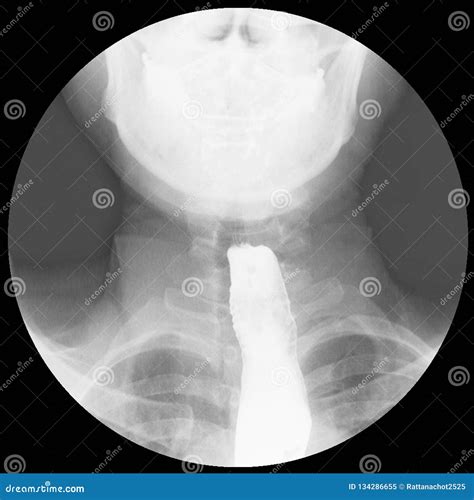

When a patient presents with dysphagia (difficulty swallowing), the Achalasia Barium Swallow serves as a cornerstone diagnostic test. During this procedure, the patient drinks a liquid containing barium, a contrast material that coats the inner lining of the esophagus. As the patient swallows, a radiologist uses fluoroscopy—a continuous X-ray beam—to observe the movement of the liquid down the esophagus in real-time.

Preparing for the procedure is relatively straightforward, but it is essential to follow your healthcare provider’s specific instructions. Generally, you will be asked to fast for several hours before the exam to ensure your esophagus is clear. The process is non-invasive and typically follows these steps:

1. Preparation: You will be asked to change into a gown and remove any jewelry or metal objects that might interfere with the X-ray images.

2. Ingestion: Under the supervision of a radiologist, you will be asked to swallow the chalky, barium-containing liquid.

3. Observation: You may be asked to swallow while standing in different positions or to lie down on the X-ray table so the radiologist can observe how gravity and body position affect the movement of the barium.

4. Imaging: The fluoroscope captures a series of images, creating a “movie” of the swallowing process, which is then analyzed for transit time and structural abnormalities.